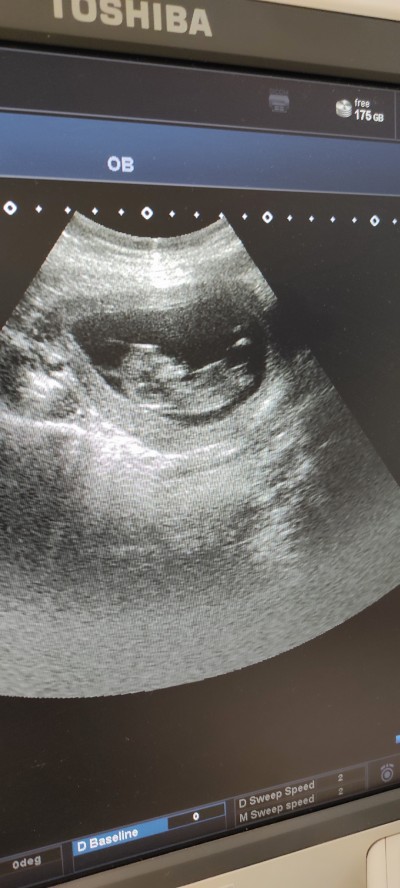

Anlayan yazabilirmi ya devlet söylemiyo cinsiyet öldürcekler adamı

Küçük haftası kiz şimdi tam belli etmiyordur belli etse pat diye söylüyorlar içimden kiz geçti

11 haftalık burda şuan 14 haftalığım salı günü kontrolüm var

Kaç haftalık kız gbi

11 haftalık resimde suan 14 haftalığım salı günü kontrolüm var

İçimden kız geçti aynı benim kızımın kesesinde böyleydi ama belli olmaz tabi

Kız gibi kesesi yuvarlak. Çin takvimine baktın mi?

Kız buuuuuu.

Keseye göre kıza benziyor canım